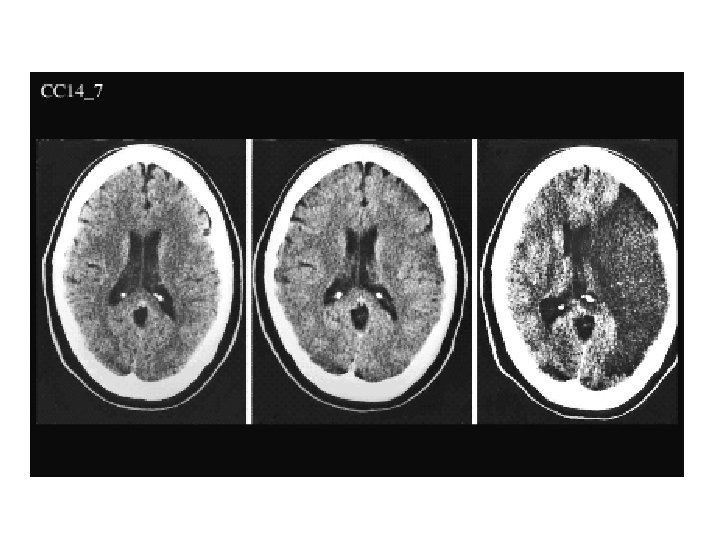

ACA PCA MCA

X 120 Anterior Comm ACA Fornix IIIrd Ventricle Thalamus & Pulvinar MCA Corpus Callosum Lateral Ventricle (Atrium) Optic Radiations Primary Visual Cortex Caudate Nuc (2 X) Internal Cap (AL, Genu, PL) Putamen Globus Pallidus (Ext & Int) External & Extreme Cap Claustrum Insular Cortex PCA

ACA MCA PCA BA VA ICA